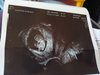

Kropek już nie przypomina kropka,ma 26mm,serducho bije jak dzwon (nawet widziałam jak pulsuje).Odetchnelam,bo przy braku klasycznych ciazowych objawów moje myśli były już bardzo różne.Ale okazuje sie,że strach ma wielkie oczy i bałam się niepotrzebnie :-) Wyliczenia dokładnie takie jak w klinice 3 tygodnie temu: mamy dziś 9t3d,termin porodu 4.01.19.Pozdrawiamy i trzymamy kciuki , znaczy na razie ja trzymam, bo mały nie-kropek jeszcze chyba nie umie :-) :-) :-)

IMG_20180604_102359.jpg

Kropek już nie przypomina kropka,ma 26mm,serducho bije jak dzwon (nawet widziałam jak pulsuje).Odetchnelam,bo przy braku klasycznych ciazowych objawów moje myśli były już bardzo różne.Ale okazuje sie,że strach ma wielkie oczy i bałam się niepotrzebnie :-) Wyliczenia dokładnie takie jak w klinice 3 tygodnie temu: mamy dziś 9t3d,termin porodu 4.01.19.Pozdrawiamy i trzymamy kciuki , znaczy na razie ja trzymam, bo mały nie-kropek jeszcze chyba nie umie :-) :-) :-)Zobacz załącznik 863656